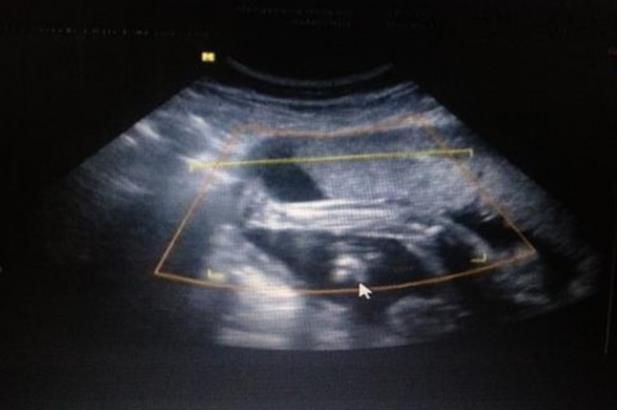

仁济医院生殖医学中心成立以来,成功率达到国内外先进水平。目前,生殖医学中心人工授精成功率稳定在20%以上,试管受精成功率约为50%。

目前上海试管婴儿的成功率平均在40-50%左右,但对于每个人的情况,成功率会有所不同。另外,成功率和年龄也有很大关系。一般年轻患者的试管成功率会高于年长患者。另外,要学会调整心态。情绪波动过大会影响下丘脑和脑垂体的功能,阻碍性腺激素分泌,导致排卵障碍。心情不好还会导致输卵管痉挛收缩,宫颈粘液分泌,影响胚胎着床。所以要做好心理准备,以最好的身体状态迎接宝宝。试管过程中如有问题,应及时与主治医生沟通,以便及时调整治疗方案。